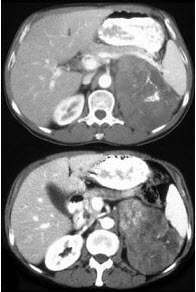

女,43岁,满月脸、皮肤紫纹、月经不规则3月余,请结合所提供图像,作出诊断( )

A:左肾上腺腺瘤

B:左肾上腺嗜铬细胞瘤

C:左肾上腺转移瘤

D:左肾上腺腺癌

E:左肾上腺增生